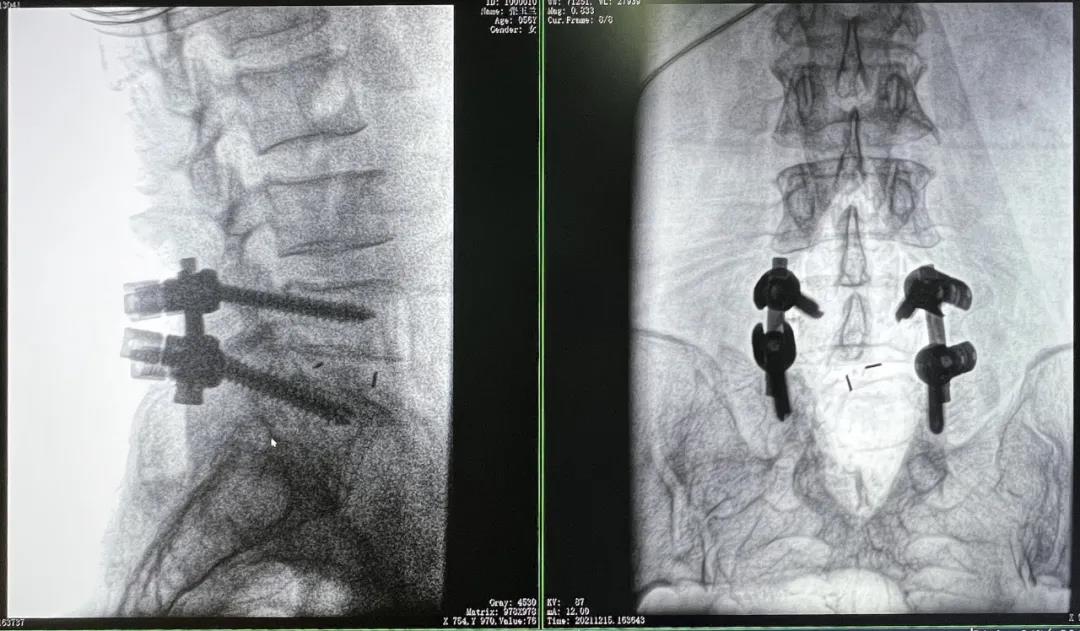

3D C形臂擺位及手術(shù)前二維影像

醫(yī)生在影像引導(dǎo)下在L5/S1椎弓根處打入醫(yī)用螺釘

術(shù)中快速生成橫斷面、矢狀面、冠狀面斷層圖像和三維立體圖像